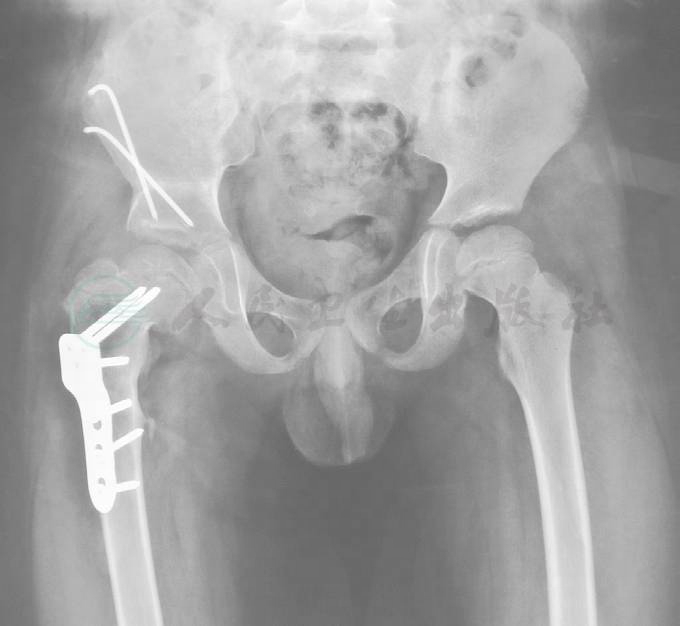

在完善相关检查及准备后,择日行手术治疗,术中采用联合术式:股骨近端内翻截骨术与骨盆Salter截骨术(图2),术后行髋人字石膏固定,术后1年复查,见股骨头塑形近球形,髋臼覆盖满意,髋关节活动范围满意(图3)。

图2 术中骨盆正位片:股骨近端内翻截骨PHP钢板固定术与骨盆Salter截骨术